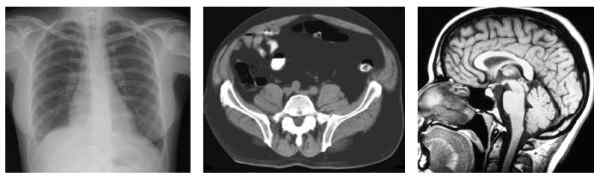

Als de anatomie van de mens of een andere diersoort beschreven wordt, is het handig om het betreffende onderwerp (mens of dier) te bestuderen en te beschrijven in de standaardanatomische positie, om verwarring tussen voor of achter en onder of boven te voorkomen. Dit is meestal de positie die mens of dier in normale omstandigheden ook aanneemt. Voor mensen is de standaardanatomische positie een rechtopstaande positie, met de voeten bij elkaar (en de tenen voorwaarts gericht), met de armen langs de zijden hangend en de handpalmen voorwaarts gericht (figuur 1). De duim is dus voor de oriëntatie anatomische gedefinieerd als het meest buitenwaarts gerichte lichaamsdeel. Links en rechts zijn altijd gedefinieerd vanuit het perspectief van de patiënt. Het hart bevindt zich dus in de linkerzijde van de thorax. Een dwarsdoorsnede wordt, tenzij anders aangegeven, vanuit het voeteneinde beschouwd. Bij een dwarsdoorsnede op thoraxniveau bevindt het hart zich dus aan de rechterzijde en de wervels zich aan de onderzijde van de afbeelding. Bij viervoeters is de standaardanatomische positie dat het dier met zijn vier poten op de grond staat, met het hoofd in een neutrale positie vooruit kijkend.

Links: röntgenfoto van de thorax in het frontale vlak; midden: CT-scan van het abdomen in het transversale vlak; rechts: MRI-scan van de hersenen in het sagittale vlak.